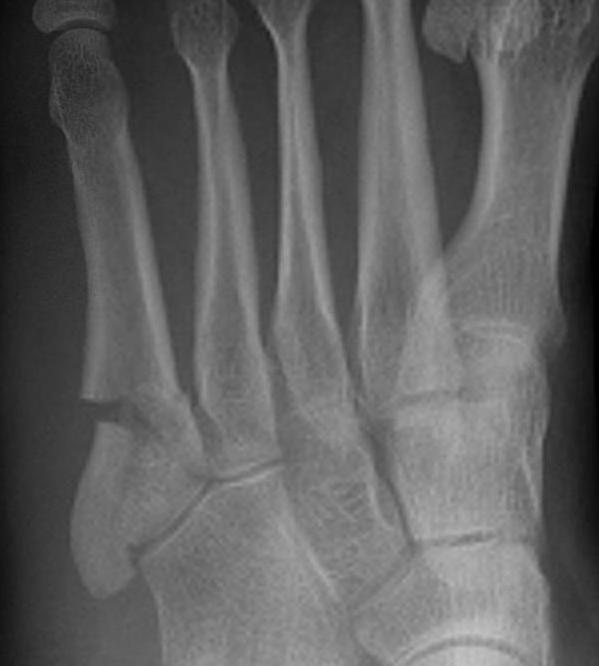

Xray

Zone 2 fractures

Union of zone 2 fracture with nonoperative care

Progression to nonunion of zone 2 fracture with nonoperative care